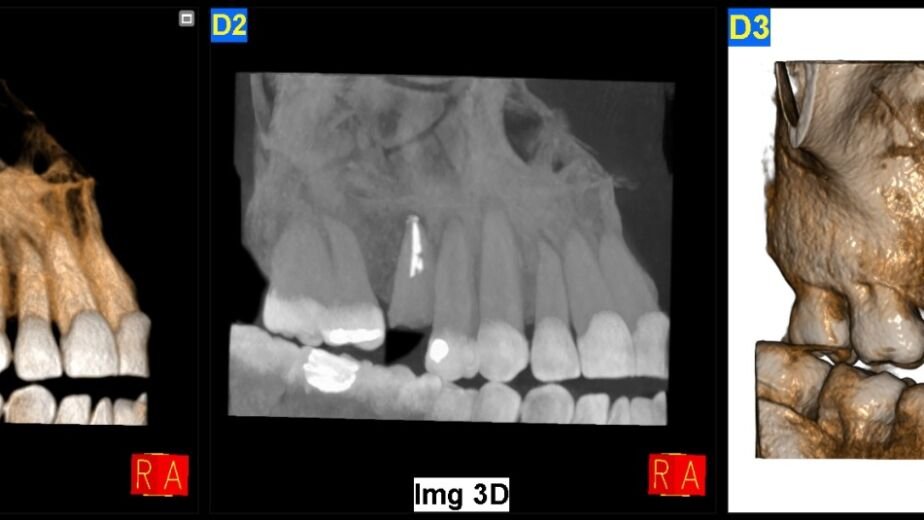

La tomografía computarizada de haz cónico (CBCT, por sus siglas en inglés) ha revolucionado la radiología facial al ofrecer imágenes tridimensionales de alta resolución con una dosis de radiación significativamente menor en comparación con las tomografías computarizadas convencionales. Este avance ha permitido a los médicos obtener una visión más clara y precisa de la anatomía facial, lo que resulta crucial para el diagnóstico y tratamiento de diversas afecciones. Por ejemplo, en odontología, el CBCT se utiliza para planificar implantes dentales, ya que proporciona información detallada sobre la densidad ósea y la ubicación de estructuras anatómicas importantes.

Además, el CBCT ha demostrado ser invaluable en la evaluación de trastornos maxilofaciales y en la planificación quirúrgica. Los cirujanos pueden utilizar estas imágenes para simular procedimientos antes de realizarlos, lo que reduce el riesgo de complicaciones y mejora los resultados postoperatorios. La capacidad de visualizar estructuras complejas en tres dimensiones ha cambiado radicalmente la forma en que se llevan a cabo las intervenciones quirúrgicas, permitiendo a los profesionales tomar decisiones más informadas y precisas.

Imágenes tridimensionales: la clave para un diagnóstico preciso en radiología facial

Las imágenes tridimensionales han emergido como una herramienta esencial en la radiología facial, proporcionando una representación más completa y realista de la anatomía del paciente. A diferencia de las radiografías bidimensionales tradicionales, las imágenes 3D permiten a los médicos observar las estructuras faciales desde múltiples ángulos, lo que facilita un diagnóstico más preciso. Esta capacidad es especialmente útil en casos complejos, como malformaciones congénitas o lesiones traumáticas, donde una visión detallada puede marcar la diferencia en el tratamiento.

Un ejemplo claro de la utilidad de las imágenes tridimensionales se encuentra en la planificación de cirugías reconstructivas. Los cirujanos pueden utilizar modelos 3D generados a partir de imágenes radiológicas para diseñar implantes personalizados o guías quirúrgicas, lo que optimiza el proceso quirúrgico y mejora los resultados estéticos. Además, estas imágenes son valiosas para la educación médica, ya que permiten a los estudiantes y profesionales visualizar y comprender mejor la anatomía facial.

La radiología facial 3D se ha convertido en un componente esencial en la planificación quirúrgica maxilofacial. Al proporcionar representaciones tridimensionales precisas de la anatomía del paciente, esta tecnología permite a los cirujanos planificar procedimientos con un nivel de detalle sin precedentes. Por ejemplo, durante una cirugía ortognática, los cirujanos pueden utilizar modelos 3D para simular diferentes enfoques quirúrgicos y predecir resultados estéticos antes de realizar cualquier intervención.

Además, esta herramienta facilita la comunicación entre el equipo quirúrgico y el paciente. Al mostrar modelos tridimensionales del rostro del paciente y explicar cómo se llevará a cabo el procedimiento, los cirujanos pueden ayudar a los pacientes a comprender mejor lo que pueden esperar. Esto no solo mejora la experiencia del paciente, sino que también fomenta una mayor confianza en el proceso quirúrgico.